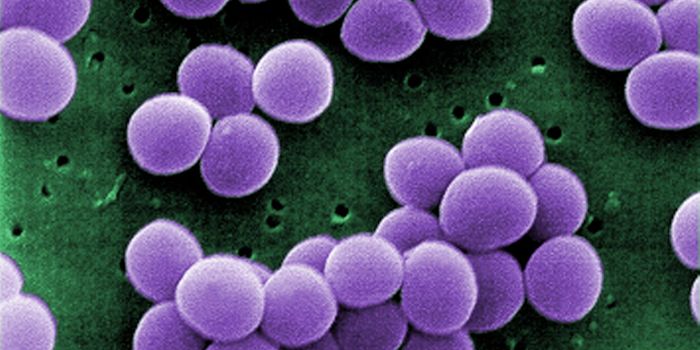

OCT 12, 2016ImmunologyThe key ingredient in the recipe that make staphylococcus and streptococcus infections so dangerous? Superantigen toxins ...

MAR 16, 2015MicrobiologyTargeting deadly, drug-resistant bacteria poses a serious challenge to researchers looking for antibiotics that can kill ...

NOV 10, 2017ImmunologyThe only way to overcome multidrug-resistant bacteria is to design a drug that bacteria have never encountered. In a new ...